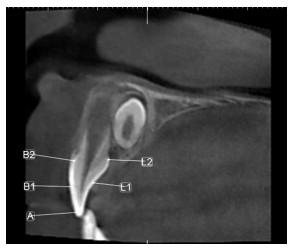

The cone-beam CT was used to compare the hardness of enamel between mesiodens and maxillary lateral incisors

GUO Zhenfei, ZHAO Lili, ZHANG Kai

2024, 22(12): 2046-2048. doi: 10.16766/j.cnki.issn.1674-4152.003794

597 3

Abstract:

Objective  The cone-beam CT (CBCT) was used to compare the hardness of enamel between mesiodens and maxillary lateral incisors and analyze the relationship between the two teeth, seeking a method of autologous tooth grafting.  Methods  PLANMECA ROMEXIS Viewer software was used to collect a total of 104 mesiodens from 75 supernumerary tooth patients in the stomatology department of the First Affiliated Hospital of Bengbu Medical University from August 2015 to July 2017. Then, the enamel hardness of mesiodens and maxillary lateral incisors were evaluated by Hounsfield units (HU). The HU values of five tooth surfaces were detected, including the incisal edge (A), the labial midpoint (B1), the midpoint of the cervical margin in the labial surface (B2), the lingual midpoint (L1) and the midpoint of the cervical margin in the lingual surface (L2).  Results  A total of 104 mesiodens were detected, of which 98 were impacted (94.2%) and 6 were erupted (5.8%). Forty-six (61.3%) had a single mesiodens, while 29 (38.7%) had two mesiodens. No significant difference was observed in the enamel hardness between the right and left maxillary lateral incisors and right and left mesiodenses (A, B1, B2, L1, L2 site, P>0.05). The enamel hardness of L1 and L2 surfaces was similar between mesiodens and the right maxillary lateral incisor (P>0.05). While, there were differences in the enamel hardness of the right maxillary lateral incisor and mesiodens at the A, B1, and B2 surfaces. It is observed that the enamel hardness of the right maxillary lateral incisor were higher than mesiodens (P < 0.001).  Conclusion  The enamel hardness is similar between mesiodens and maxillary lateral incisor. Mesiodens with normal shapes may be an ideal substitute for missing maxillary incisors.